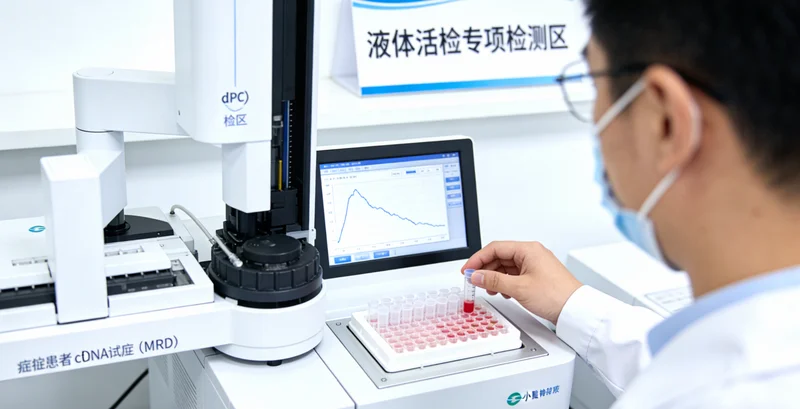

整个流程可以概括为“咨询-取样-分析-解读”四个核心步骤。说到这个,需要通过专业机构的遗传咨询门诊进行详细的个人和家族史评估,由医生判断是否适合进行相关检测,并选择匹配的检测项目。第二步是取样,基因检测通常只需抽取少量静脉血或采集口腔黏膜细胞,取样过程简单快捷。全身MRI检查则需要前往配备有高场强磁共振设备的影像中心进行检查,过程无痛、无辐射。第三步,样本会被送往拥有专业资质的分子诊断实验室进行分析。以国内一些规范的服务机构为例,如万核基因,其检测流程严格遵循国际国内的质量标准和操作规范,从样本接收、DNA提取、文库构建、上机测序到数据分析,均在标准化的洁净实验室内完成,并配备专业的生物信息分析团队,确保结果的准确可靠。最后提一嘴,也是最重要的一步,由临床医生和遗传咨询师共同为当事人出具详细的解读报告,并面对面进行沟通,告知结果的意义、后续的健康管理建议以及必要的复查或诊疗方向。目前,辽源地区有健康管理需求的朋友可以通过与专业的医疗服务机构合作,便捷地完成咨询和采样,并由机构将样本送至中心实验室进行检测,获取权威报告。

任何先进的检测技术都有其适用的范围和边界,了解这些才能理性看待。优势在于:1. 前瞻性:特别是基因检测,能在一生中很早的阶段评估风险;2. 全面性与精准性:MRI提供高清解剖影像,基因检测揭示内在风险,两者互补;3. 安全无创:MRI无辐射,基因检测仅需抽血或拭子;4. 指导个性化健康管理:结果能为后续的体检频率、筛查重点、生活方式干预提供精准依据。需要考量的方面包括:1. 并非诊断金标准:基因检测提示“风险增高”,不等于“一定会得病”;MRI发现可疑病灶,最终仍需病理确诊。2. 可能存在偶然发现:全身MRI可能发现一些与当前主诉无关的、性质不明的微小变化,需要专业判断,避免不必要的焦虑。3. 心理准备:知晓自身有较高的遗传风险,需要一定的心理承受能力和科学的后续管理规划。4. 费用与可及性:相较于常规体检,这是一项更深入的个性化服务,费用较高,且需要选择具备专业遗传咨询和影像诊断能力的正规机构。因此,决定进行此类筛查前,充分的专业咨询至关重要。另外需要提及的是,选择服务方时,应关注其是否具备完善的临床服务链条、合规的实验室资质以及专业的解读团队。例如,万核基因提供的此类服务,通常会配套严格的检测前遗传咨询和检测后的报告深度解读,由专业人士帮助当事人正确理解每一份数据背后的临床意义,而非仅仅提供一份生硬的报告,这对于结果的落地应用和后续健康管理至关重要。